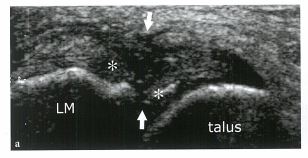

▶좌측: 정상 ATFL 인대 ▶우측: 부분파열된 ATFL 인대 (※출처:근골격계 초음파. Stefano bianchii, Carlo Martinoli)

좌측 그림에서 화살표로 표시되어있는 부분이 정상적인 전거비인대입니다. 뼈와 뼈 사이를 수평하게 잇고, 섬유의 texture와 에코도가 일정하죠. 그와 비교하여 우측 그림을 보시면 중간의 인대섬유가 끊어지고, 부어있는 모습이 보입니다. 에코도 어두워지고 지저분해져있죠. 상처가 난 부위입니다.